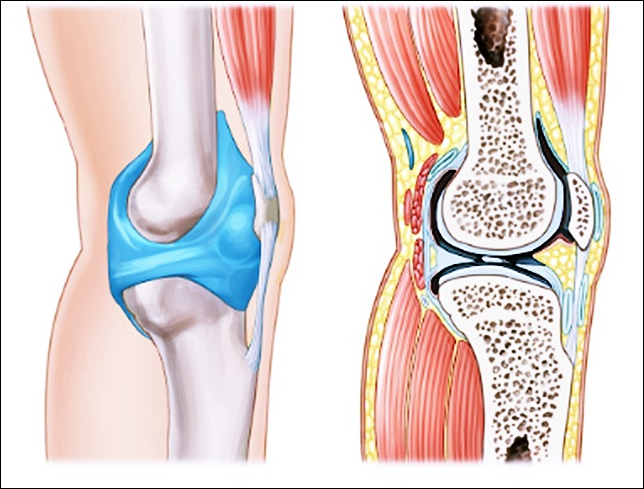

안녕하세요. 클릭 궁금해결소 입니다. 오늘은 관절염과 관절통증 개선에 효과적인 종근당 이모튼 캡슐에 대한 정보를 낱낱이 파헤쳐보도록 하겠습니다. 그동안 관절 불편한 증상으로 인해 고생하셨나요? 그렇다면 잘 오셨습니다. 아래에서 여러분의 지긋지긋한 관절염과 통증개선에 도움이 될만한 정보를 얻어가시기 바랍니다. 구체적인 사항이 궁금하시다면 아래를 참조하세요.

종근당 이모튼 캡슐의 효능은 크게 두가지가 있습니다. 퇴행성 관절염을 포함한 골관절염에 효과가 있습니다. 그리고 치주질환에도 도움이 됩니다. 치주질환으로 발생한 출혈과 통증을 제어하기 위한 보조적인 요법으로 활용될 수 있습니다. 그렇다면 종근당 이모튼 캡슐은 어떻게 복용해야 안전할까요? 다음을 참고하세요.